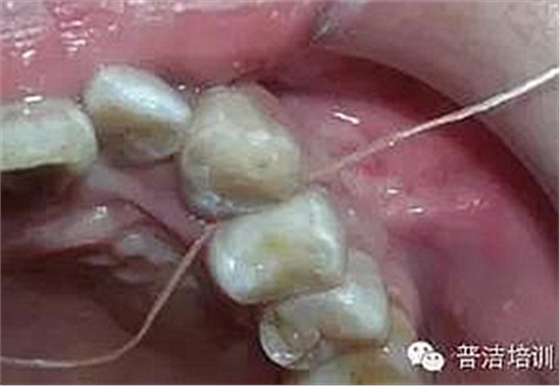

十四、完全就位前去除多余的水門汀,并用牙線和探針仔細去除牙齒之間的多余材料。

牙線去除鄰面樹脂粘結(jié)劑

鄰面拋光